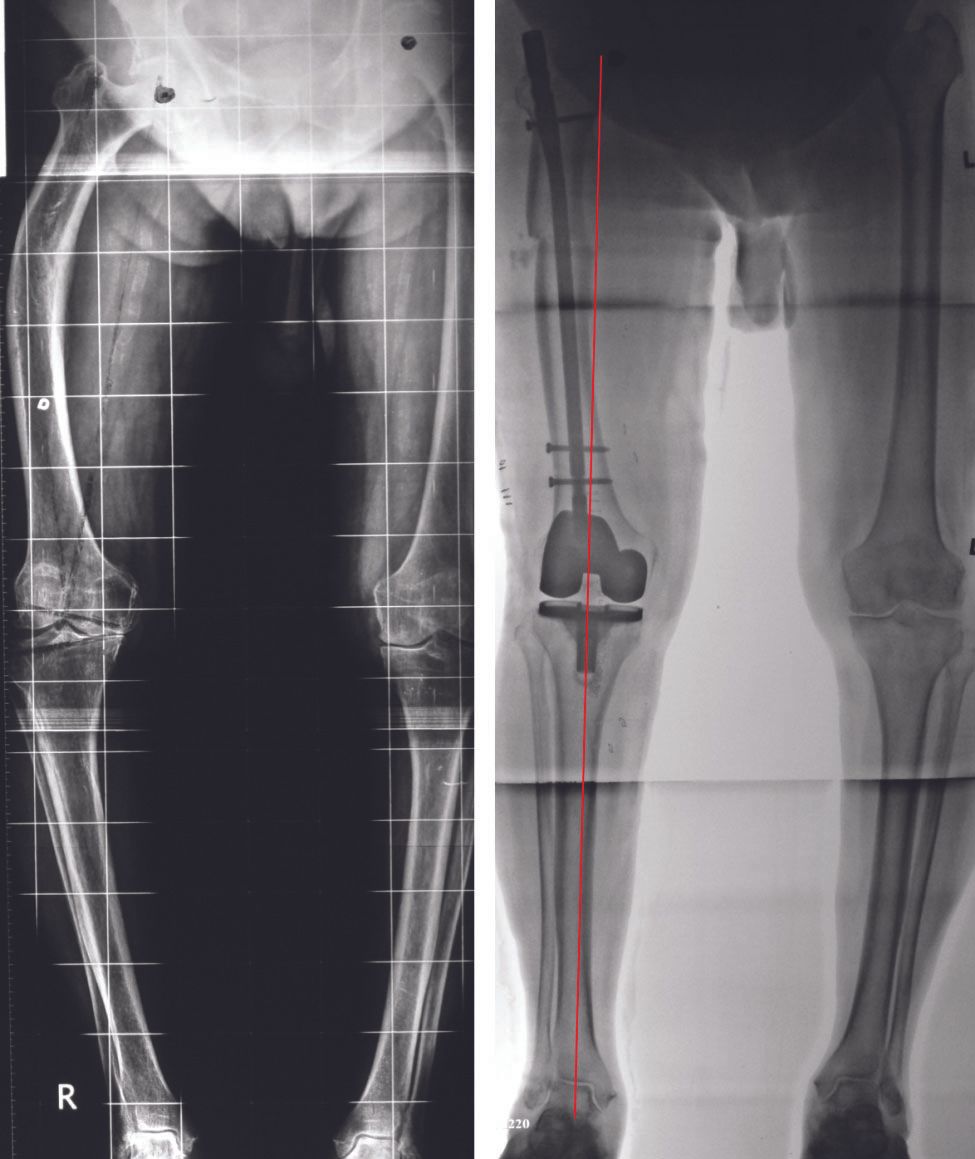

3. Extra-articular femoral and/or tibial deformity needs to be identified and appropriate extra-articular or intra-articular correction performed8

If extra-articular deformity (EAD) is >20 degrees, close to the joint, and resection likely to damage LCL attachment or if the distal tibial axis falls outside of tibial plateau, then EA osteotomy may be required.(Figs 4-6)

In the presence of femoral EAD, a persistent trapezoidal extension gap is addressed by distally sliding the medial condyle by the amount required to equalise medial and lateral gaps in extension. As the condyle is not slid anteriorly or posteriorly, it does not affect the flexion gap symmetry.

- If these are released and deformity persists, it implies that there is a tibial EAD. This should have been detected and anticipated in the planning stage. Obtain a rectangular extension gap by re-cutting proximal tibia. Any residual varus deformity is corrected by closed-wedge osteotomy at apex of deformity usually in the tibial metaphysis.